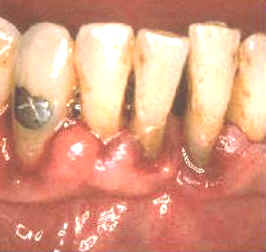

La imagen  muestra la condición 3 semanas después del tratamiento. La curación ha progresado pero algo más de placa puede observarse en comparación al fotograma anterior. El paciente ha reducido el control químico de placa bacteriana  por el sabor amargo del cclorhexidine.  Para conservar a menudo el resultado del tratamiento es necesario que el paciente realice el control químico de la placa bacteriana a intervalos regulares y debe mantener un correcto cepillado dental. El éxito del tratamiento depende fundamentalmente de la colaboración del paciente en su hábito higiénico.